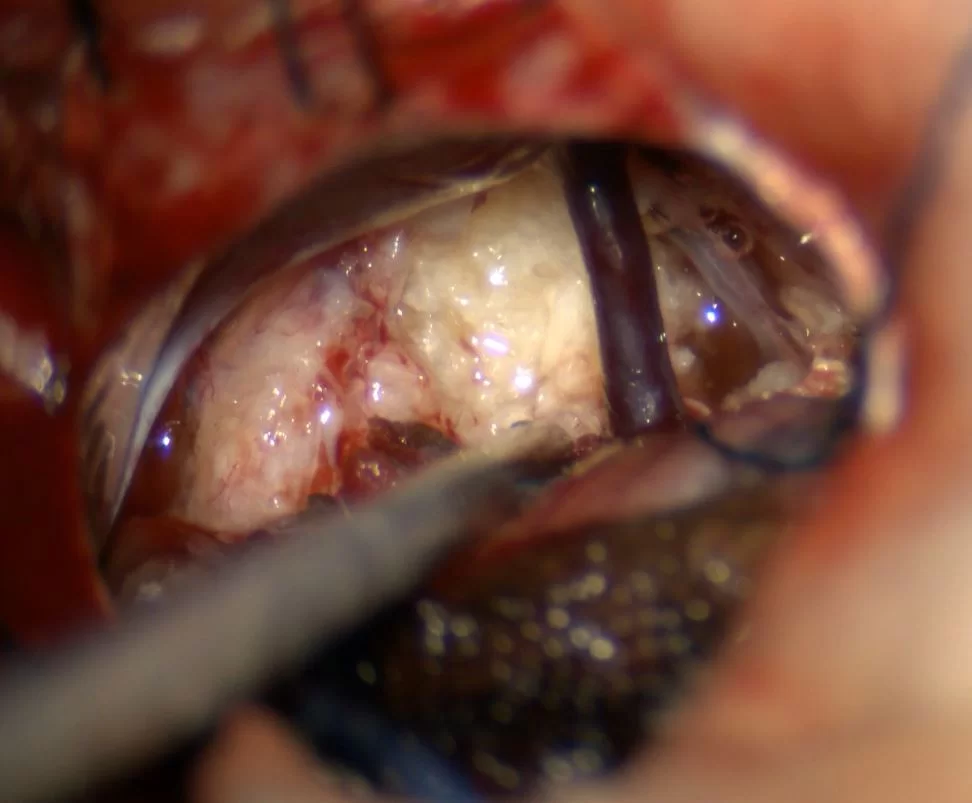

Οι επιδερμοειδείς κύστεις αντιμετωπίζονται με χειρουργική επέμβαση. Οι κύστεις τείνουν να αναπτύσσονται κατά μήκος των κρανιακών νεύρων, πράγμα που μπορεί να καταστήσει την ολική αφαίρεσή τους δύσκολη. Διεγχειρητικά, έχουν χαρακτηριστική εμφάνιση, σαν “πέρλα” (Εικόνα 1). Για πολλαπλές ή ταχέως επαναλαμβανόμενες επιδερμοειδείς κύστεις έχει περιγραφεί η θεραπεία με ακτινοβολία.